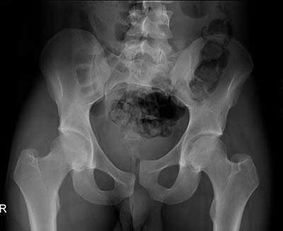

骶尾骨骨折要休息多長時間會好呢,在這期間骨折患者應(yīng)該如何注意自己的飲食呢?那么,請點(diǎn)擊馬上鏈接康復(fù)熱線 骶神經(jīng)損傷嚴(yán)重時可出現(xiàn)跟腱反射消失,但很少出現(xiàn)括約肌功能障礙,予后與神經(jīng)損傷程度有關(guān),輕度損傷予后好,一般一年內(nèi)可望恢復(fù)。